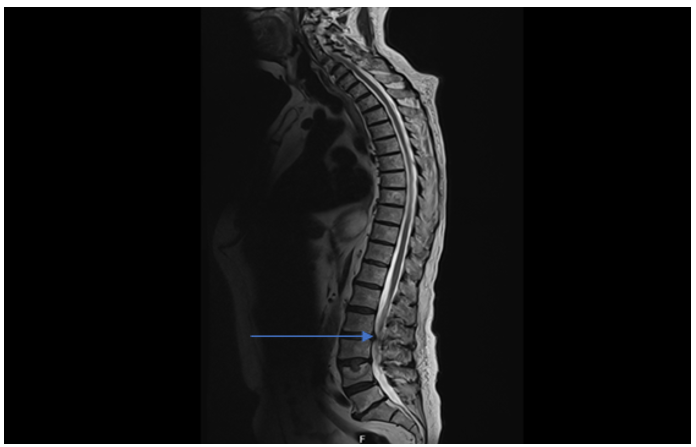

Initially, it was unclear whether the presence of spinal metastasis was the primary cause of the postural drop. However, after an MRI, it became more apparent that the level of stenosis the patient had was the main contributing factor to the postural drop. However, an MRI of the entire spine revealed the presence of spinal stenosis and cauda equina without any accompanying symptoms of spinal disease. This discovery led to the diagnosis of autonomic neuropathy as the underlying cause of the patient's postural drop

An MRI spine was performed given metastatic spread to the vertebra evident in CTAP, MRI spine (figure 3) showed T3/ T4 lesion with significant spinal canal stenosis and cauda equine impairment, with no cord compression. Neurological examination is normal, with no neurological deficit or pathology. The patient was discussed with neurosurgery and was transferred under their care for further management.

Figure 3: MRI whole spine showing metastatic deposits resulting in significant canal stenosis and impingement of cauda equine (blue arrow). Severe posterior disc protrusion at level L3/L4 causing significant canal stenosis and impinging of cauda equina with right sided predominance. Multiple marrow replacing metastatic deposits with no evidence of cord compression